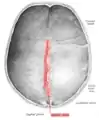

La suture sagittale

Vue interne de la suture sagittale.